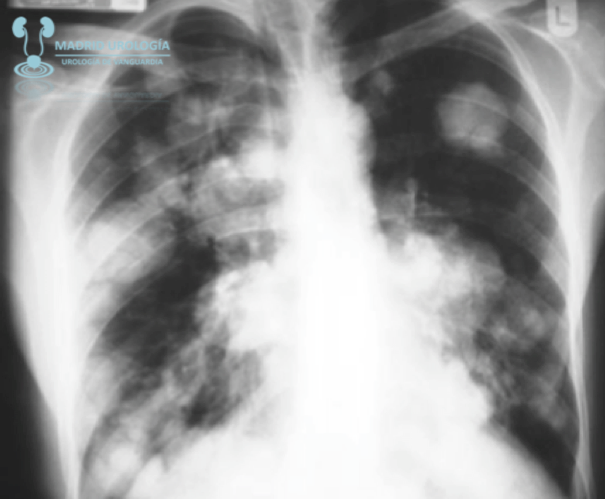

TAC TORAX

El TAC de tórax debe realizarse en todos lo casos de TCG No Seminomatoso y podría ser omitido en casos de TCG Seminomatoso sin afectación de metástasis infra diafragmáticas.

Según las guías de la EAU

El TAC de tórax se recomienda en todos los casos de TCG independientemente de la estirpe fundamentado en que un 10 % de los casos se presentan con nódulos subpleurales no detectables mediante radiológia simple.

El TAC de tórax tiene Alta Sensibilidad pero No Especificidad.

| Metástasis pulmonares en suelta de globos en un caso de TCG No Seminomatoso. Recuerde que en un 10 % de los casos las imagenes de nóduoos pulmonares no son valorables mediante radiología simple. |